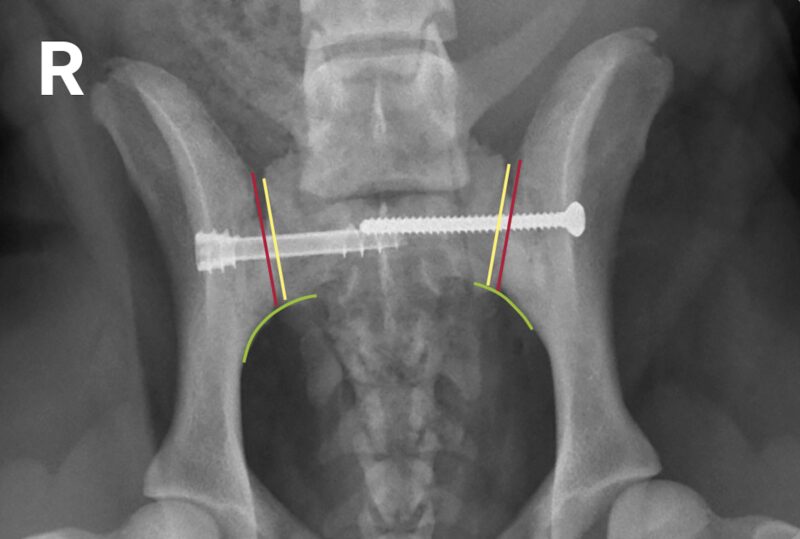

In Folge eines Autounfalls erlitt ein 2 Jahre alter Podenco (weiblich) ein Trauma und kann seitdem nicht mehr gehen. Auch stehfähig ist der Patient nur mit Unterstützung. Der klinische Befund ist links schlechter als rechts. Der Röntgenbefund zeigt eine Schambein- und Sitzbeinfraktur links mit Symphysenfraktur bzw. Symphysiolyse. Zu erkennen ist eine bilaterale iliosakrale Luxation mit langerungsbedingt variabler Darstellung. Die Aufnahmen geben damit Antwort auf die nach einem Unfall häufige Frage, ob das Iliosakralgelenk luxiert ist und eine Diastase vorliegt oder nicht. Eine normale anatomische Situation zeigt stufenlose Gelenkflächenkonturen von Darmbein (Ilium) und Sakrumflügel sowie einen schmalen Gelenkspalt.

Der Befund ergibt eine iliosakrale Luxation bzw. Diastase. Die Stufe in den Konturen zeigt die Luxation des Darmbeins nach kranial (grün). Die Verbreiterung des Gelenkspalts zeigt die Dislokation des Darmbeins nach lateral (gelb).